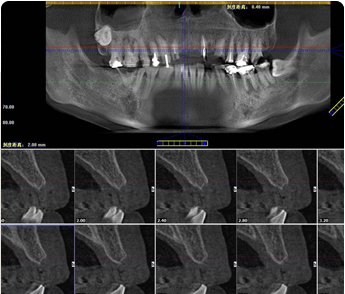

锥形束平板CT:

360°3D口腔透视

CT数据+种植医生

+3D种植模拟软件

智能导航,3D种植导板定位

数字化3D导板定位植体深度、角度,微孔植入创口牙根大小